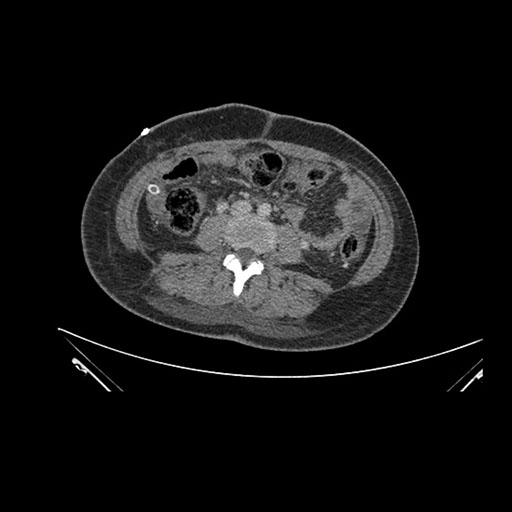

Imaging Analysis

Look through the patient's CT scan to identify any areas of concern for the necessary procedure.

Axial Venous

Based on initial findings, which issue(s) would you be most concerned about?